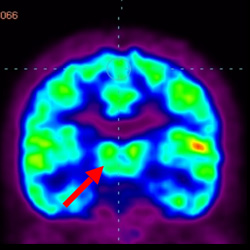

細胞治療前PET CT掃描顯示神經(jīng)組織中的藍/黑色區域,表明腦癱引起的大腦損傷。

細胞治療后,藍色和黑色區域減少,并且看到更活躍的區域。這表明損傷減少并改善了大腦功能。

細胞治療前 PET CT 掃描顯示神經(jīng)組織中的藍/黑色區域,表明腦癱引起的大腦損傷。

這證明細胞療法是治療腦癱兒童安全有效的方法。細胞療法可以更新大腦損傷的核心,并且可以通過(guò) PET CT 掃描來(lái)監測大腦的改善情況。這些細胞療法與標準治療一起促進(jìn)腦癱兒童的生長(cháng)和改善。